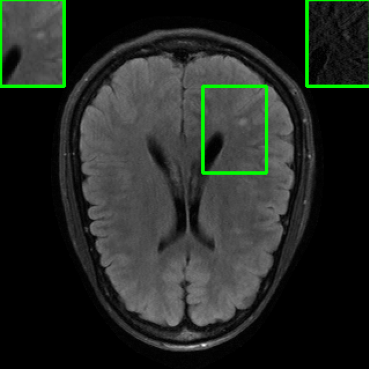

Performance on Data with Lesions: While the previous experiment allowed comparing reconstruction quality with or without planted features, here we test our method on MRI scans with lesions, which are often regions of abnormal or diseased tissue. We utilize the annotated fastMRI+ data666https://github.com/microsoft/fastmri-plus/tree/main to evaluate our method’s image reconstruction capabilities, and compare its outcomes with established baselines. For the training phase, the non-lesion dataset was employed for the global training approach with images whereas LONDN-MRI used adaptively selected images for training (searched from images). In contrast, during the testing phase, we used scans with lesions. The results, as displayed in Table V, indicate that our method achieves substantially higher PSNR values in comparison to the globally trained baseline as well as the LORAKI method. Furthermore, visualizations in Figure 16 clearly demonstrate the superiority of our method, particularly in the nonspecific white matter lesion areas. Thus, both in terms of visual assessment and PSNR values, our approach outperforms the existing baselines and aligns more closely with the ground truth.

| Ground Truth | LORAKI | Global | LONDN-MRI | LONDN-MRI | Oracle |

| (1 iteration) | (2 iterations) | ||||

![]() |

| PSNR = dB | PSNR = 33.17 dB | PSNR = 35.10 dB | PSNR = 35.67 dB | PSNR = 35.74 dB | PSNR = 35.87 dB |